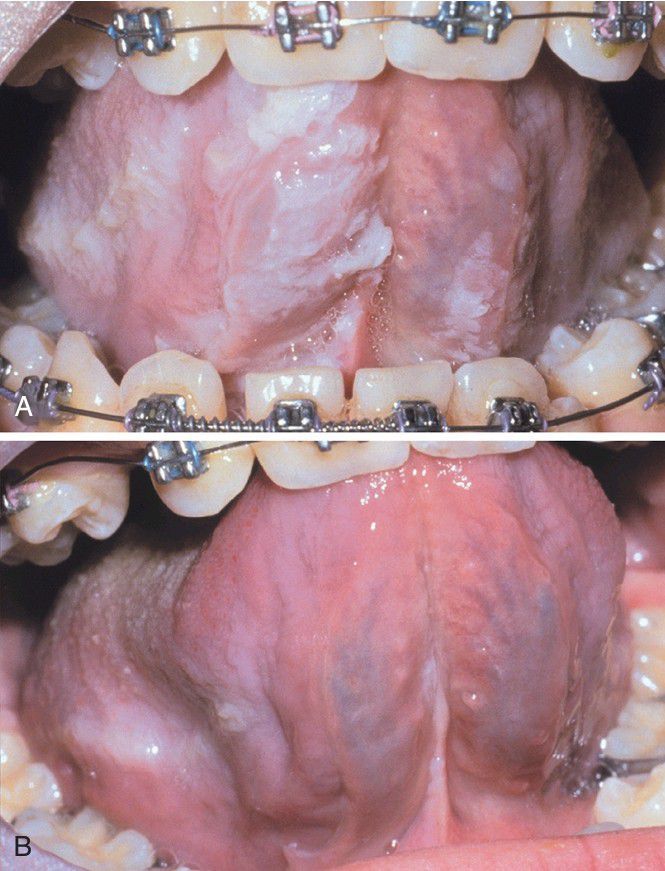

Uremic Stomatitis.

A, Ragged white plaques affect the ventral tongue and floor of the mouth. B, Same patient after renal dialysis.